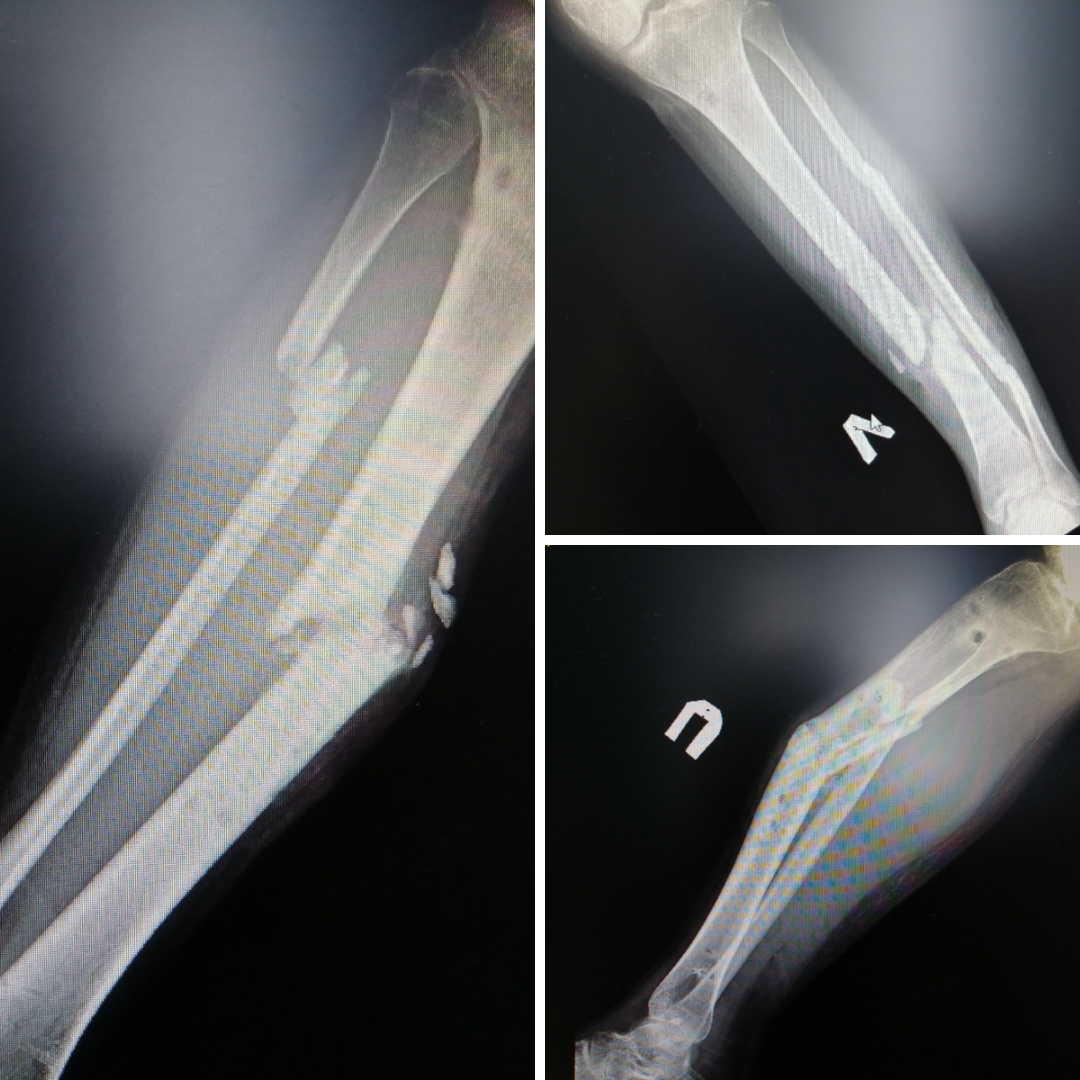

20-летний пациент оказался в травмбольнице после 8-ми месяцев безуспешного лечения за пределами Сургута. Травмы голеней молодой человек получил в ДТП. Несмотря на использование внешнего фиксатора – аппарата Илизарова – костные отломки так и не срослись. Более того, появилась деформация, образовались ложные суставы. На момент госпитализации ходить пациент не мог и передвигался в инвалидном кресле. Наши специалисты провели полный комплекс обследований и определили план лечения.

– Со второй голенью, деформация которой была более выраженной, дела обстояли сложнее. Пациенту снова наложили аппарат Илизарова, чтобы растянуть костные отломки и добиться их репозиции, – объясняет заведующий отделением ортопедо-травматологическим отделением №4 Евгений Бойко.